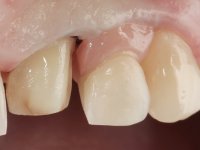

This addition of resin would guide the ceramist in the final placement of the gingival tonality ceramic. The crown that would rehabilitate tooth 1.3 was cemented in this test session with glass ionomer cement, reinforced with composite resin. Once the laboratory work was finished on the veneer for tooth 1.2, the abutment, and the veneer for the implant, this was bonded in the mouth, after placement of the absolute insulation. The work completely satisfied the patient. For eight years, the patient had periodical check-ups, and was pleased with the treatment, but also began to show interest in an aesthetical intervention on the upper central incisors. Once the second phase of our intervention was decided, dental preparation of teeth 1.1 and 2.1 was performed for the placement of two feldspathic veneers. Particular care was taken in the distal inter-proximal preparation adjacent to the abutment of the implant.

The axis of insertion of the veneer in relation to the abutment was very carefully evaluated. The feldspathic veneers were prepared in the laboratory and then bonded to the mouth after placing absolute insulation. One year later, we began our third phase of treatment, after the veneer in tooth 2.1 fractured. A dental preparation was done on the bonded veneer, seeking to extend the distal inter-proximal interface more to the palate. The objective would be to move the veneer to a more palatine contact point. Preparation of tooth 1.2 was limited to creating an insertion axis. After preparation, the total crown and laboratory veneer were bonded to the mouth. First, the crown was bonded using a relative insulation with Teflon, later the veneer was bonded after the absolute insulation placement. In the crown, I used this type of insulation to avoid the use of staples. It would be difficult to apply due to the shape and size of the tooth, and would also be aggressive to the soft tissues. After bonding procedures, the occlusal integration of the work was evaluated.